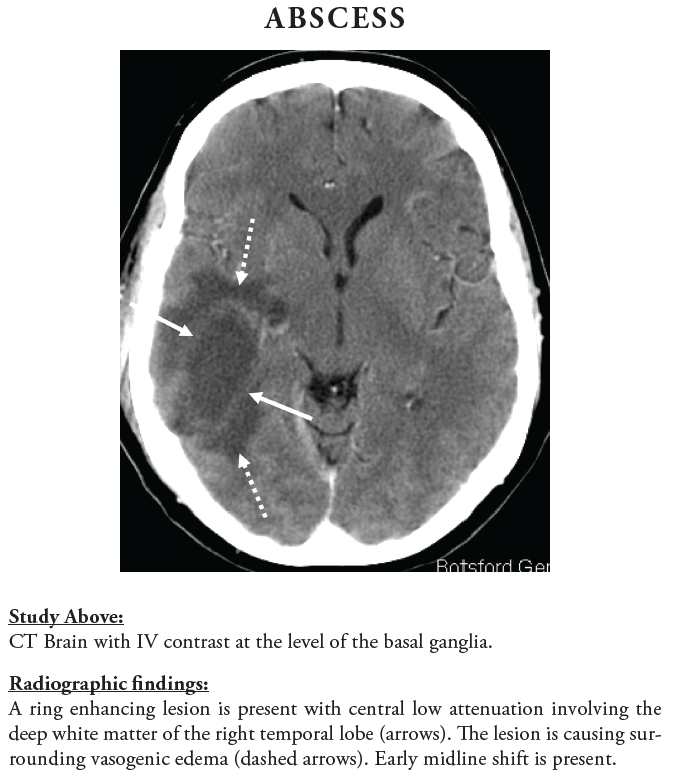

✨Up Next in our Member Spotlight Series - featuring Dr. Rocky Saenz! His passion for education has inspired numerous medical students and radiology residents. Dr. Saenz has made significant strides for DOs and radiologists, enhancing their recognition in the medical field.